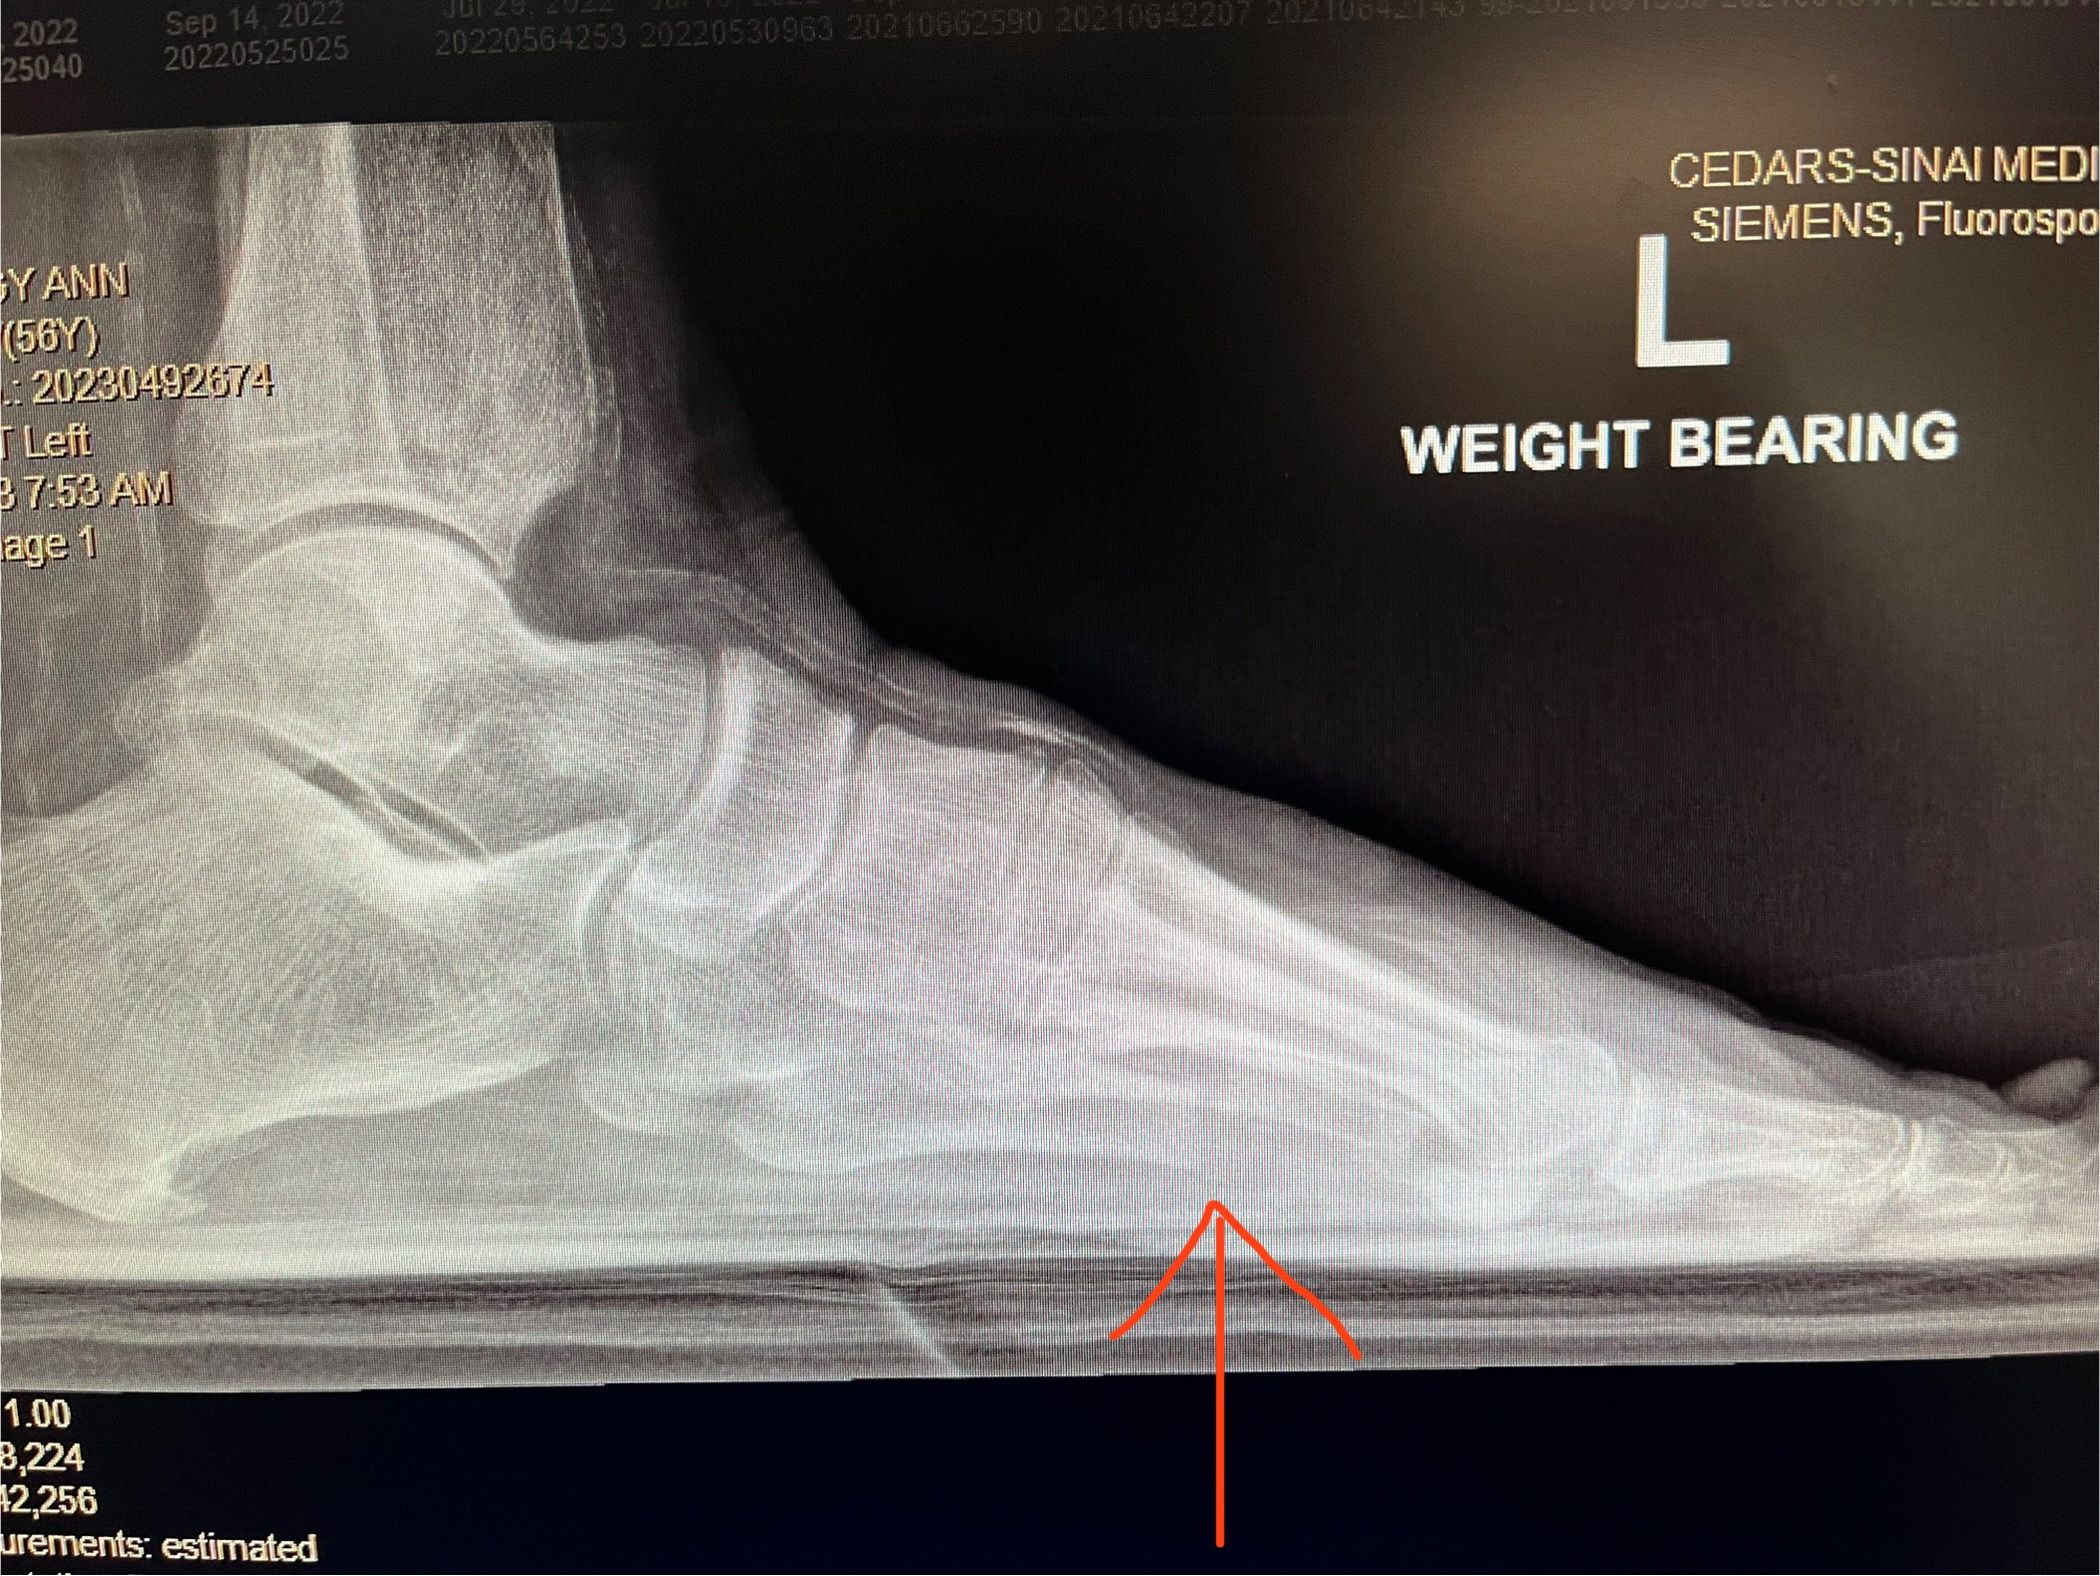

בצילום שלמטה אפשר לראות מהצד איך העצם עולה למעלה ולמעשה מורידה את הלחץ על מנת לתת לפצע להחלים.